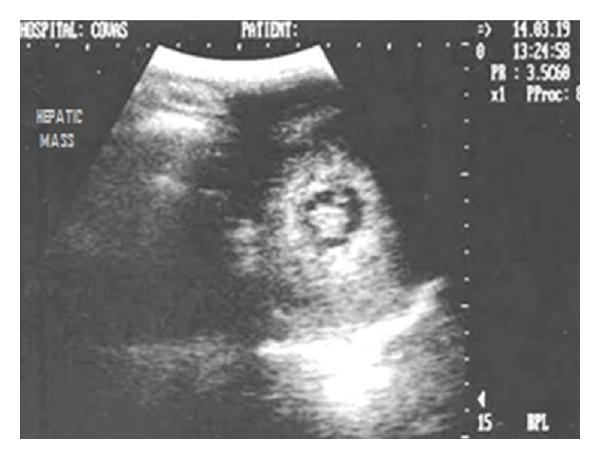

Hepatic disease is often treatable and has a predictable prognosis when a definitive diagnosis is made. The aim of clinicopathological evaluation of hepatobiliary affections is to identify and characterize hepatic damage and dysfunction, identify possible primary causes of secondary liver disease, differentiate causes of icterus, evaluate potential anaesthetic risks, assess prognosis and response to xenobiotics, and monitor response to therapy. This paper describes the different diagnostic methods and imaging techniques employed in diagnosis of hepatobiliary affections in dogs. Besides reviewing the significant clinical manifestations and imaging structural abnormalities in diagnostic approach to different hepatic affections, it also depicts radiographic, ultrasonographic, and wherever applicable, the laparoscopic characterization of different hepatic affections and target lesions encountered in clinical cases presented in the Teaching Veterinary Clinical Complex, COVAS, Palampur in the year 2007-2008.

肝病通常是可治疗的,一旦做出明确诊断,其预后是可预测的。肝胆疾病临床病理评估的目的是识别和描述肝损伤及功能障碍,确定继发性肝病可能的主要病因,鉴别黄疸的病因,评估潜在的麻醉风险,评估预后及对外源化学物质的反应,并监测治疗反应。本文描述了用于诊断犬肝胆疾病的不同诊断方法和成像技术。除了回顾不同肝病诊断方法中的重要临床表现和成像结构异常外,还描述了2007 - 2008年在帕兰普尔兽医临床综合教学中心(COVAS)出现的临床病例中不同肝病及目标病变的放射学、超声学特征,以及在适用情况下的腹腔镜特征。